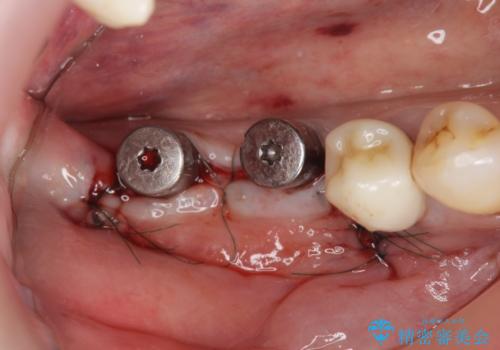

- 81.4万円 (straumann社製インプラント×2 アバットメント×2 仮歯×2 骨造成 ジルコニアクラウン×2)費用は治療当時の料金となります

入れ歯に替わりインプラント治療を行ったことでしっかりと物が噛め、食事ができるようになり大変喜んでいただくことができました。